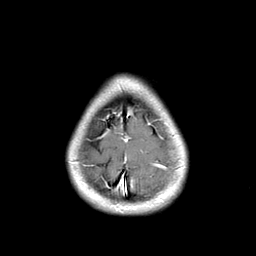

Metastatic bronchogenic carcinoma: T1-weighted MR -- Slice #21

[Home][Help][Clinical] Slice 21